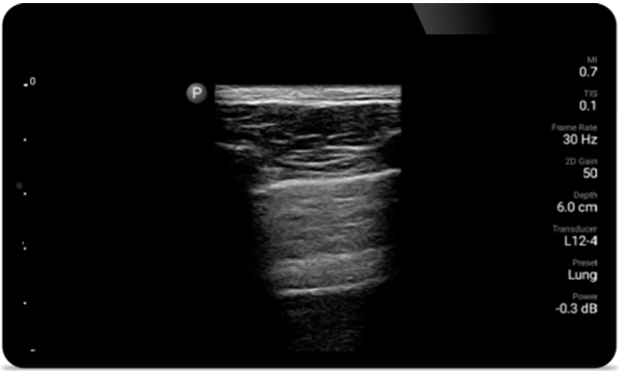

Lumify can help assess patients faster and improve accuracy when diagnosing common causes of dyspnea and other lung conditions.